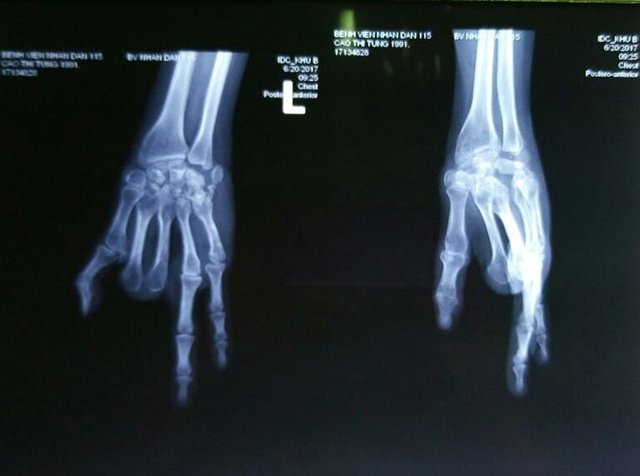

Ghép thành công hai ngón chân thành hai ngón tay cho một phụ nữ

Sau 7 năm bị cụt mất ngón tay do tai nạn lao động, bệnh nhân đã được bác sĩ lấy hai ngón chân ghép lên...